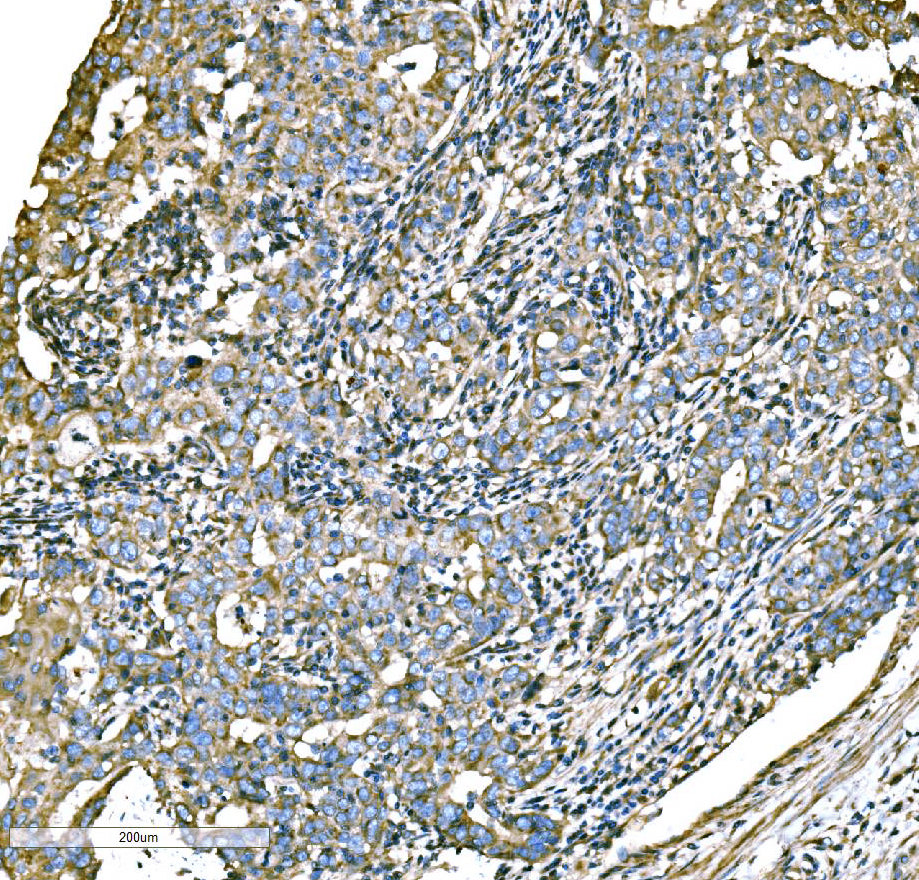

IHC analysis of ATG16L1 using anti-ATG16L1 antibody (A00526-3).

ATG16L1 was detected in a paraffin-embedded section of human lung cancer tissue. Biotinylated goat anti-rabbit IgG was used as secondary antibody. The tissue section was incubated with rabbit anti-ATG16L1 Antibody (A00526-3) at a dilution of 1:200 and developed using Strepavidin-Biotin-Complex (SABC) (Catalog # SA1022) with DAB (Catalog # AR1027) as the chromogen.